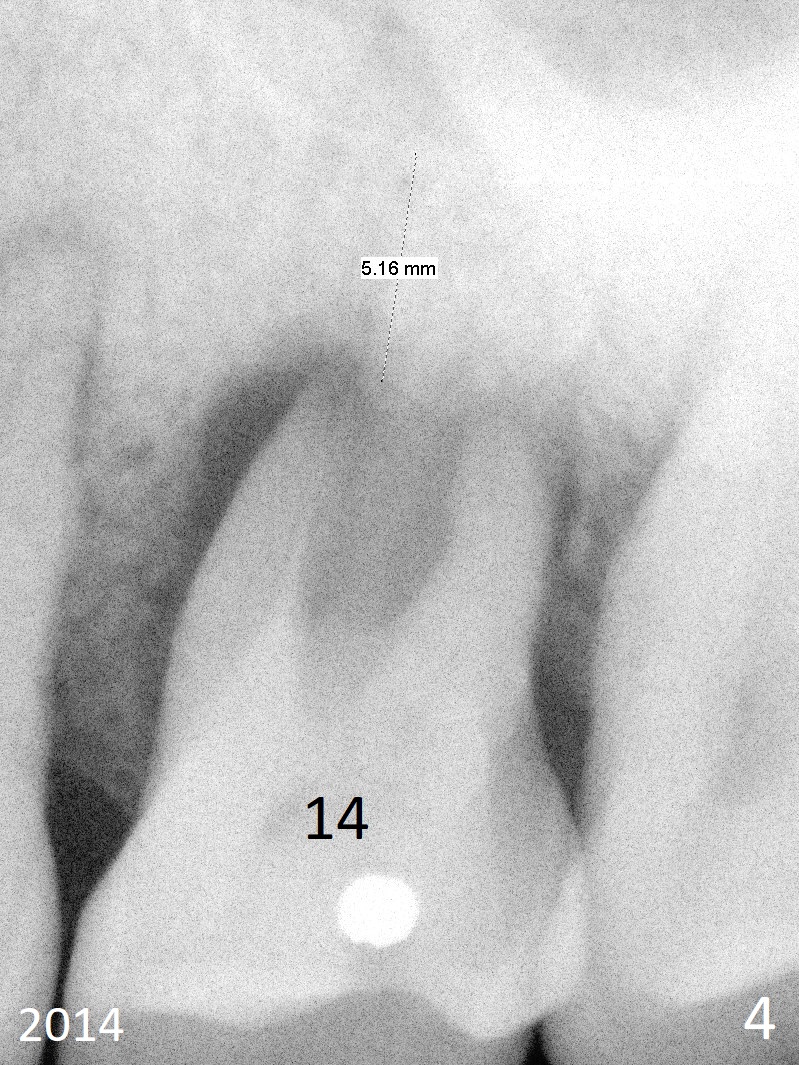

A 48-year-old woman has generalized moderate localized (#3,14) advanced periodontitis (Fig.1). The edentulous area at #6 has been restored. Now the tooth #3 has mobility III (Fig.2), while #14 has exfoliated (Fig.3,4). If the tooth #3 is symptomatic, extract it for immediate implant. Otherwise use Magic Split to initiate access and osteotomy expansion, followed by Magic Expanders (3.0 and 3.8 mm) or Magic Sinus Lifter. Insert Tatum tapered taps. If the gingiva is excessively long, switch to UF implant for mill abutment.